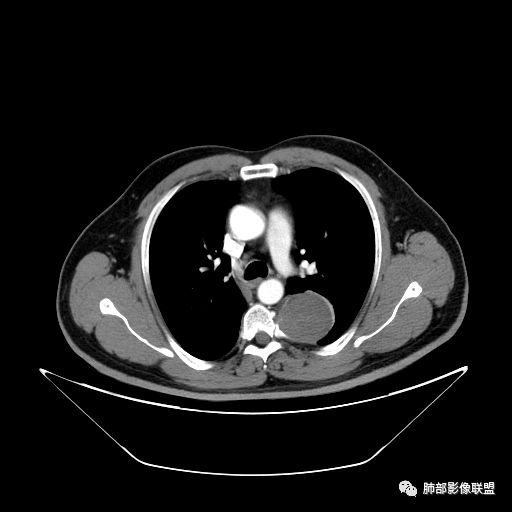

曹志勇:右肺尖后段类圆形病灶,边界清边,缘锐利,宽基底与胸膜相连,环形强化,内似见蛇纹血管征,考虑胸膜孤立性纤维瘤,右肺外底段病灶,考虑炎性可能大

红日东升:左侧胸椎旁肿块,边缘清晰光整,冠状位见D字征,未见支气管进入,肺组织受压表现,定位肺外。轻度强化,密度稍不均匀,临近肋骨变细,未见肺动脉供血,考虑良性肿瘤,神经源性可能。右肺下叶病灶,轻度强化,血管显影,边缘平直、凹陷,考虑炎性病变。

左肺下叶脊柱旁病灶,可见胸膜尾征,均匀强化,临近椎间孔未见扩大,考虑孤立纤维瘤,鉴别诊断神经源性肿瘤,右肺下叶病灶边缘平直,明显均匀强化,边缘清楚,考虑机化性肺炎。

张帅:患者中年男性,咳嗽 咳痰3月,痰为白色粘痰,左上肺病灶,边缘光滑,周围未见毛刺 分叶,肺组织受挤压,与胸膜关系密切,部分层面与胸膜脂肪间隙消失,有胸膜尾征,病灶定位于胸膜,病灶增强可见强化,边缘可见增强血管,内可见低密度区,考虑 孤立胸膜纤维瘤?神经鞘瘤?右肺下叶外基底段病灶,病灶与胸膜有牵拉,病灶边缘光滑,平直 u型征,未见明显毛刺,增强病灶内可见增强血管影,边缘低密度,考虑病灶内存在痰栓。右下肺病灶考虑良性炎症性病灶,ABPA?

张立:左侧胸椎旁肿块,边缘清晰光整,冠状位见D字征,未见支气管进入,肺组织受压表现,定位肺外。轻度强化,密度稍不均匀,,未见肺动脉供血,神经源性肿瘤,节细胞神经瘤可能。右肺下叶病灶,轻度强化,血管显影,边缘平直、凹陷,TB可能。

可芸:定位:肺外病变,胸椎旁肿块,边缘清晰光整,可见胸膜尾征无支气管进入,肺组织受压。轻度强化,密度稍不均匀,未见肺动脉供血,考虑良性肿瘤,神经源性,孤立性纤维瘤?右肺下叶病灶,轻度强化,血管显影,边缘平直、凹陷,炎性病变。

王秀仙:左侧后纵膈占位,位于胸膜下,胸膜被顶起,有胸膜尾征,密度均匀,轻度强化,内可见斑点钙化。周围肺组织结构推移。右肺下叶可见片状影,沿支气管走行,边缘平直收缩,强化明显,胸膜有牵拉。二元论,考虑1左侧后纵膈神经鞘瘤。鉴别SFT.2右肺下叶炎性肉芽肿。

心灵鸡汤:先定位再定性,左侧胸椎旁沟见一团状软组织影,边清,密度均,推挤周围组织,增强轻度强化,考虑为良性肿瘤,来源于后纵隔神经源性的肿瘤,神经鞘瘤可能,鉴别孤立性纤维瘤,孤立性真菌类。左肺下叶外基底段斑片影,倾向机化性肺炎或慢性炎症可能。请老师指点

王江涛:左侧脊柱旁软组织肿块,边界清楚,肺外胸膜来源,肺组织受压,增强有强化,考虑SFT大于鞘瘤;右肺下叶斑片影,明显强化,考虑炎性病灶。

李志国:左侧椎旁团块,宽基底、胸膜掀起,定位肺外,增强轻度强化,有蛇纹血管征,考虑孤立性纤维瘤,鉴别神经源性肿瘤

等待戈多:左侧脊柱旁软组织肿块,边界清楚,肺外胸膜来源,肺组织受压,增强有强化,考虑SFT 鉴别神经源性肿瘤;右肺下叶斑片影,明显强化,边缘平直 考虑炎性病灶。

三生石上:左侧脊柱旁软组织肿块,边界清楚,考虑神经源性肿瘤

薏米:左下近脊柱旁可见一结节状密度增高影,肺外,边界清,边缘规整,无分叶,无毛刺,无棘突,宽基底与胸膜相连,不均匀轻度强化,考虑为良性病变,神经源性可能性大,为神经鞘瘤,鉴别孤立性神经纤维瘤,神经节瘤,右肺片装密度增高影,考虑为炎症可能性大

崇军:左侧胸椎旁肿块,边缘清晰光整,有胸膜尾征,冠状位为D字征,定位肺外。轻度强化,密度稍不均匀,似乎看到肋间动脉供血,未见肺动脉供血,考虑良性肿瘤,神经源性可能。右肺下叶病灶,轻度强化,血管显影,边缘平直、凹陷,层面太少,暂时考虑炎性病变。

1.左上胸内脊柱旁半圆形肿块,质地坚实,密度比较均匀。

2.病灶周边见胸膜掀起,应当考虑胸壁或是纵隔来源,肺内病变不会如此。

3.降主动脉这一相对固定结构向前方推移,提示病灶相对坚实且有牢固附着点,不支持来自柔软的肺组织。

就如同在腹部,能将肾脏推移的包块,应该来自腹膜后。

4.可疑肋间动脉病供血,提示肿块来自后纵隔的可能性。

5.相邻椎间孔未见扩大,也未见块影延入椎管,易起自于神经根的鞘瘤似乎找不到相关支持点。

6.未提供矢状位骨窗图像,如在肋骨内下缘观察到压迹有助于肋间神经的鞘瘤的判断,这是因为二者之间密切的毗邻关系。

7.静脉期轻度强化,注意不是环形强化,亦未显示明确的“AB区”,神经鞘瘤与副节瘤亦未找到支持点。

综上,病灶定位胸壁或后纵隔,就发病率而言,神经源性可能性较大。